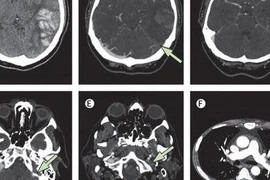

Biểu hiện huyết khối trên phim chụp.